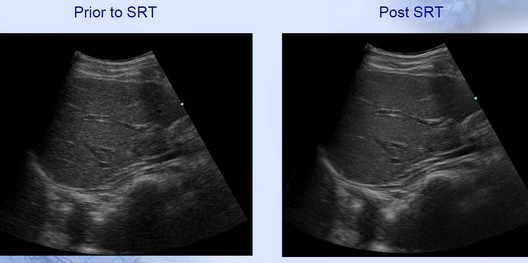

Imagenes con tecnología SRT(Speckle Reduction Technology):

• Suprimir los ruidos de echos

• Minimizar los granos de imagen

• Caracterización de tejido automatico

• Mejora la resolución de imagen

• Purifica el contorno de tejido

• Ayuda indentificación temprana de tejido con estructura de lesion